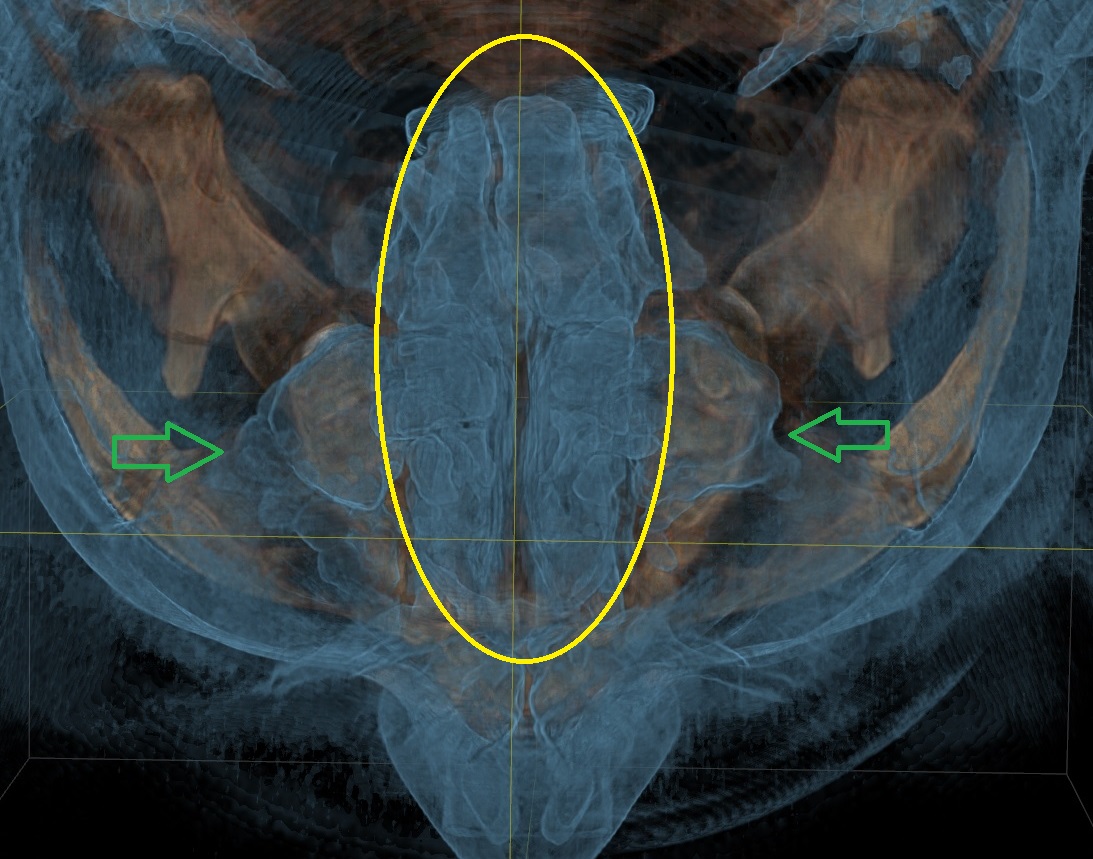

КТ-снимки хронического этмоидита: подробная визуализация

Раздел: Фотодневник открытий